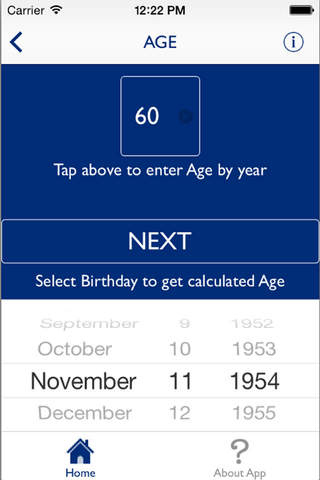

The HeRS (Hemorrhage Risk Stratification) calculator is an application that aids in determining the probability of hemorrhagic transformation of acute ischemic stroke in patients with an indication for anticoagulation. It is a prospectively validated score.

The HeRS score is a prospectively validated equation based on continuous variables of age, renal function, and stroke size. The equation is complex and cannot be performed easily or quickly with paper or with an ordinary calculator. Determining the probability of hemorrhagic transformation of acute ischemic stroke is clinically useful as risk of hemorrhage often needs to be weighed against risk of recurrent stroke in deciding on whether or not to anticoagulate in the acute clinical setting. The HeRS score provides one of these valuable pieces of data- the likelihood of hemorrhagic transformation. Using the mobile application, the HeRS score can be accurately and easily determined rapidly.

The HeRS score is a prospectively validated equation based on continuous variables of age, renal function, and stroke size. The equation is complex and cannot be performed easily or quickly with paper or with an ordinary calculator. Determining the probability of hemorrhagic transformation of acute ischemic stroke is clinically useful as risk of hemorrhage often needs to be weighed against risk of recurrent stroke in deciding on whether or not to anticoagulate in the acute clinical setting. The HeRS score provides one of these valuable pieces of data- the likelihood of hemorrhagic transformation. Using the mobile application, the HeRS score can be accurately and easily determined rapidly.